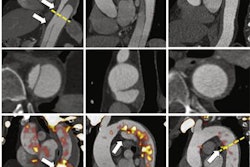

Therefore, they set out to explore NaF-PET/CT's efficacy by prospectively enrolling 81 consecutive patients (mean, 65 years; range, 47-77 years) with newly diagnosed, intermediate- and high-risk prostate cancer and with no indication of bone metastases on standard bone scintigraphy. Two physicians evaluated the NaF-PET/CT results with no knowledge of patients' clinical information or bone scintigraphy findings.

Their consensus review found no evidence of bone metastases among 73 prostate cancer patients (90.1%). Conversely, NaF-PET/CT revealed a bone metastasis in only one patient (1.2%) that was missed on scintigraphy. The researchers noted equivocal findings in the remaining seven patients (8.6%).